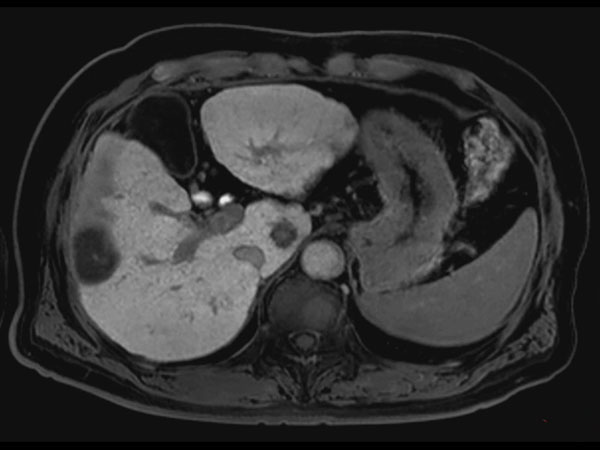

Axial Diffusion